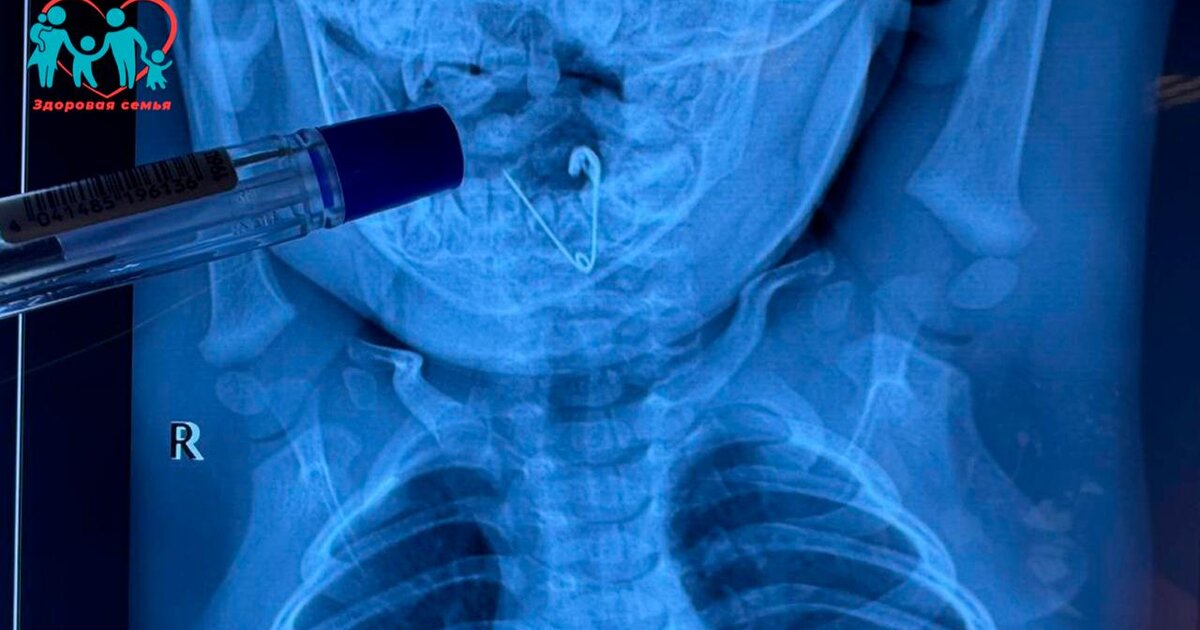

ок проглотил кольцо

Ребенок проглотил кольцо 116 фото